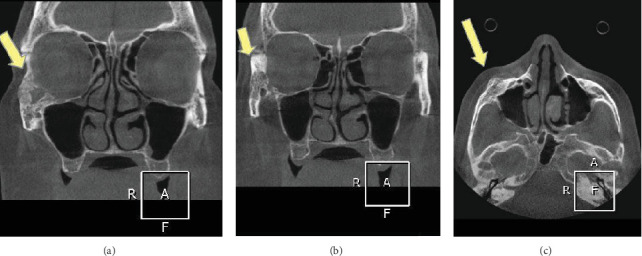

中枢性血管瘤是一种罕见的颌骨病变,患病率在0.5%至1%之间。它更常见于脊柱和颅骨,很少发生在颌骨。世界卫生组织将血管瘤归类为真正的内皮源性肿瘤;然而,一些作者认为血管瘤是错构瘤。由于其不同的临床和影像学特征,这种病变的诊断可能具有挑战性。由于受影响区域存在广泛的血管网络,治疗也很困难。在这篇文章中,我们提出了一个57岁女性颧骨中央血管瘤的病例,通过手术切除治疗。

Central hemangioma is one of the rare lesions of the jawbones, with a prevalence ranging between 0.5% and 1%. It more commonly occurs in the vertebral column and cranial bones, with rare occurrences in the jaws. The World Health Organization classifies hemangioma as a true neoplasm of endothelial origin; however, some authors believe that hemangiomas are hamartomas. Diagnosis of this lesion can be challenging due to its varying clinical and radiographic characteristics. Treatment is also difficult due to the presence of an extensive vascular network in the affected area. In this article, we present a case of central hemangioma in the body of the zygomatic bone of a 57-year-old female, which was treated through surgical resection.